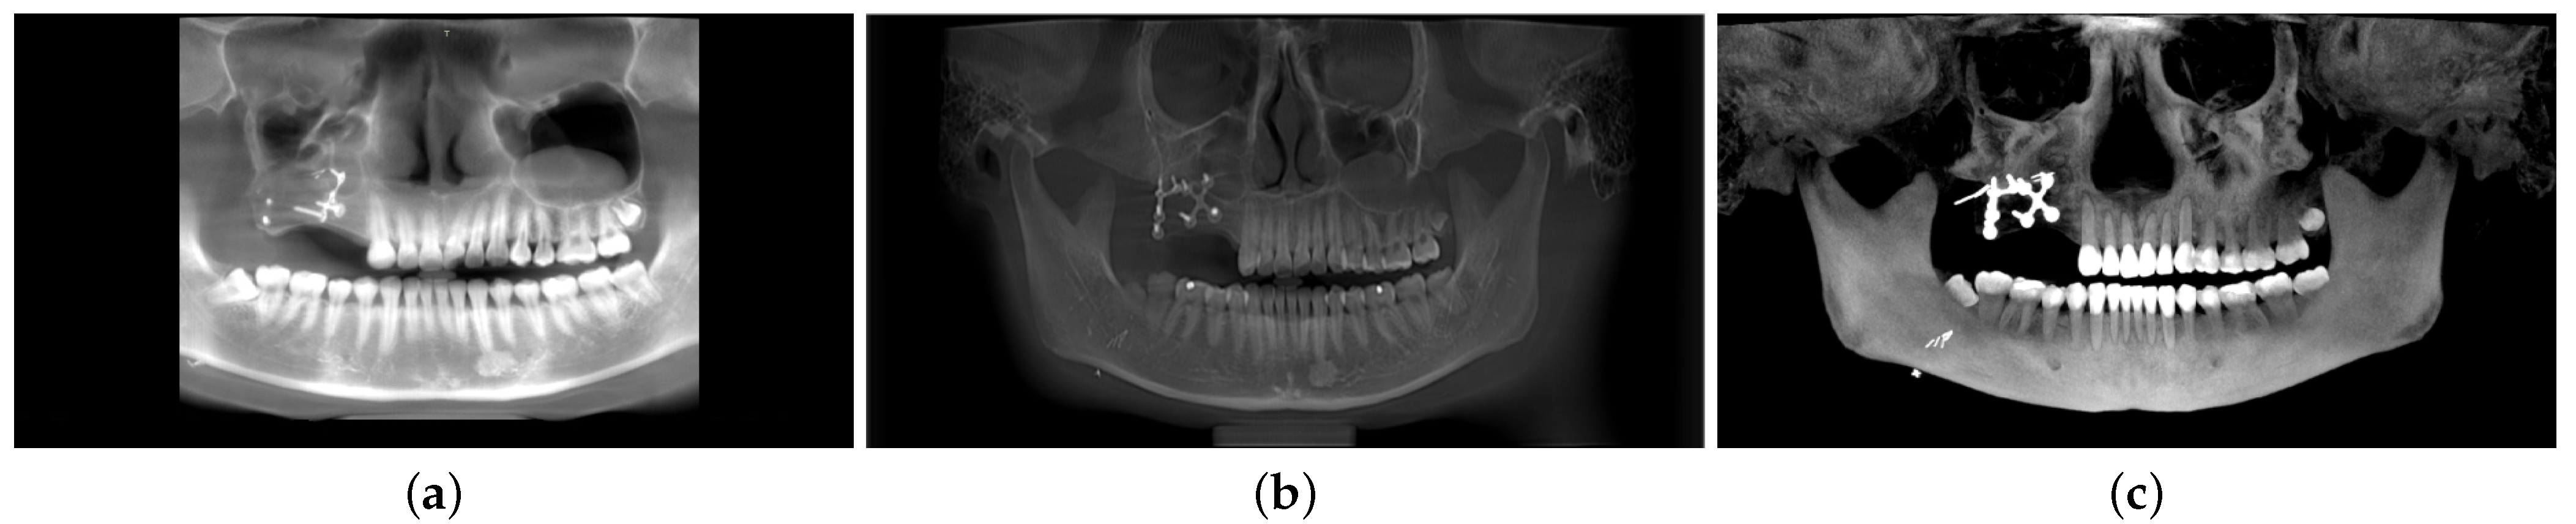

In Figure 7, we present a comparison of our proposed model with two state-of-the-art systems, BlueSky and OpenInventor. The BlueSky results display an incomplete panoramic image, with the TMJ section missing. On the other hand, the OpenInventor result presents a full panoramic image, but the dental teeth contour is not clearly visible. In contrast, our proposed method excels in reconstructing the panoramic view with enhanced details. The proposed model reveals a clear contour for each tooth, enabling a distinct differentiation between the teeth’s root and crown sections. Additionally, our proposed method exhibits significantly reduced computation time compared to OpenInventor. Specifically, OpenInventor requires a total of 634 s for processing a CBCT scan with dimensions of 559 × 450 × 559. In contrast, our proposed model achieves the same task in just 64 s, which is approximately 10 times faster than OpenInventor.

Figure 7.

Performance comparison: DeAPIR vs. state-of-the-art software (a) BlueSkyPlan, (b) OpenInventor, (c) DeAPIR.